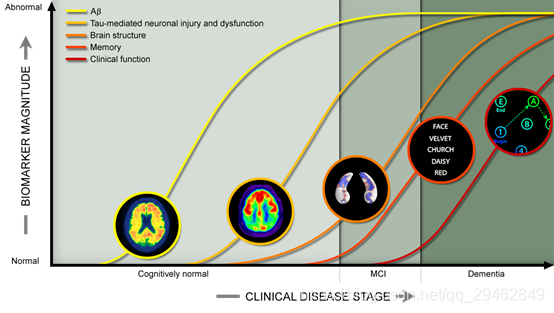

四、阿尔茨海默氏病神经影像数据

数据下载链接:http://adni.loni.usc.edu/data-samples/access-data/

数据介绍:阿尔茨海默氏病患者和健康对照的MRI数据库。 还具有临床,基因组和生物制造商数据。

ADNI:阿尔茨海默病神经影像学倡议(ADNI)研究人员从志愿者研究参与者那里收集了几种类型的数据。数据可免费提供给授权的调查员,但需要申请并事先批准。